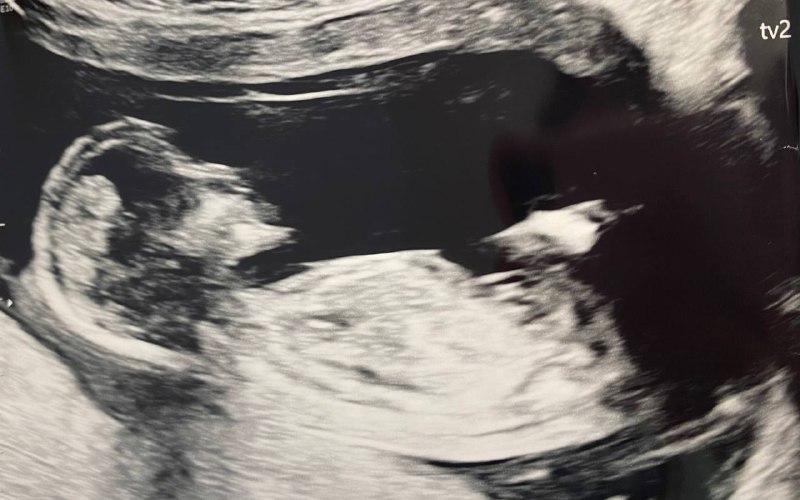

I was TTC boy and yesterday on ultrasound it showed to be identical twins. any guess about the gender?

Oh gosh I'm thinking boys here! The pics aren't terribly clear but I feel like I see nubs heading up!! FXFXFX!

I’m thinking twin boys based on the top picture.

Boys